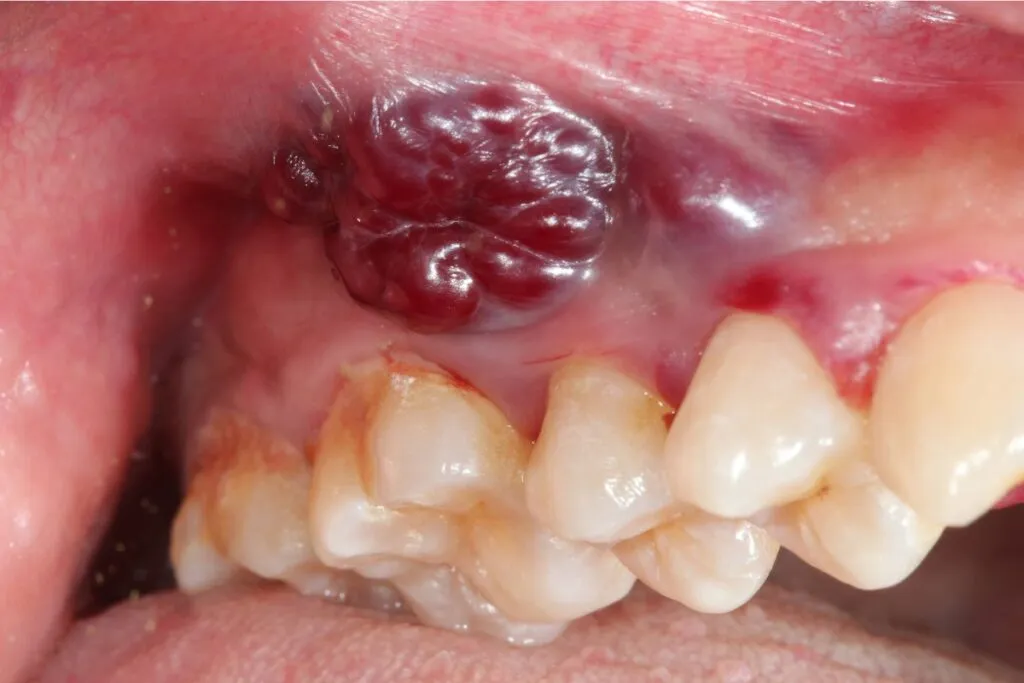

Guzki, zgrubienia i nietypowe przebarwienia

Podczas codziennej higieny jamy ustnej warto zwracać uwagę na wszelkie wyczuwalne lub widoczne guzki i zgrubienia. Mogą one pojawić się na języku (szczególnie na jego bocznych krawędziach), wewnętrznej stronie policzka, na dziąśle lub w dnie jamy ustnej. Czasem są to subtelne, twarde zmiany pod powierzchnią błony śluzowej. Niepokojące są również nietypowe przebarwienia błony śluzowej, które nie znikają i nie są związane z jedzeniem czy piciem. Pamiętaj, że wczesne stadium raka często manifestuje się właśnie takimi, pozornie niegroźnymi, zmianami w teksturze czy kolorze.

Zmiany nowotworowe na dziąsłach mogą być mylone ze zwykłym zapaleniem dziąseł. Jednak w przypadku raka, mamy do czynienia z niegojącymi się zmianami, które nie reagują na standardowe leczenie stomatologiczne. Mogą to być nietypowe zgrubienia, owrzodzenia, a także przebarwienia dziąseł (białe lub czerwone), które nie znikają. W zaawansowanych stadiach może dojść do rozchwiania zębów w okolicy zmiany.